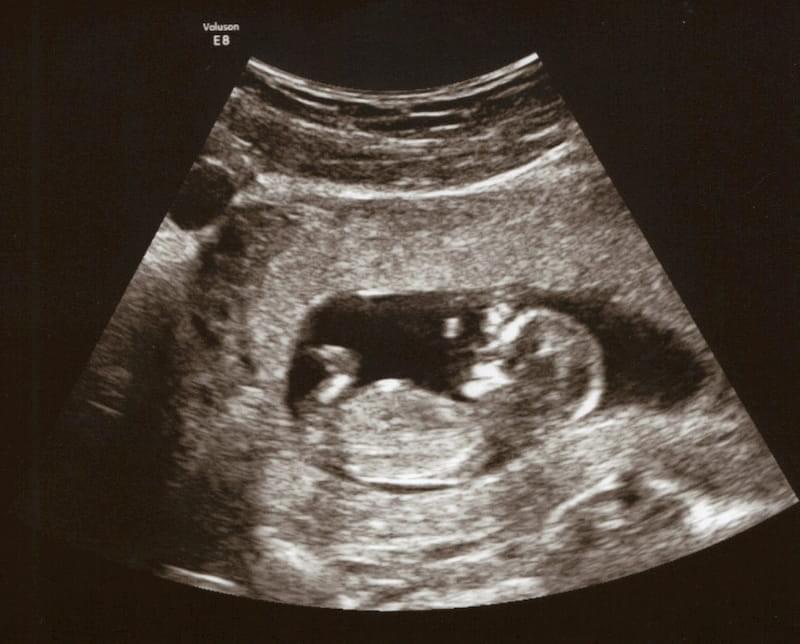

Плод начинает понемногу открывать и сжимать кулачки, приоткрывает рот. Вырастают ногти на руках и ногах, формируется наружное ухо, зачатки зубов. Репродуктивные органы ребенка также развиваются, но пол ребенка на УЗИ пока трудно определить.

«Экватор» считается самым приятным этапом: исчезает токсикоз и другие неприятные симптомы ранней беременности. В этом месяце у ребенка начнут развиваться черты лица, будущая мама чувствует движения малыша. Уже можно узнать пол ребенка на УЗИ (после 20 недель).